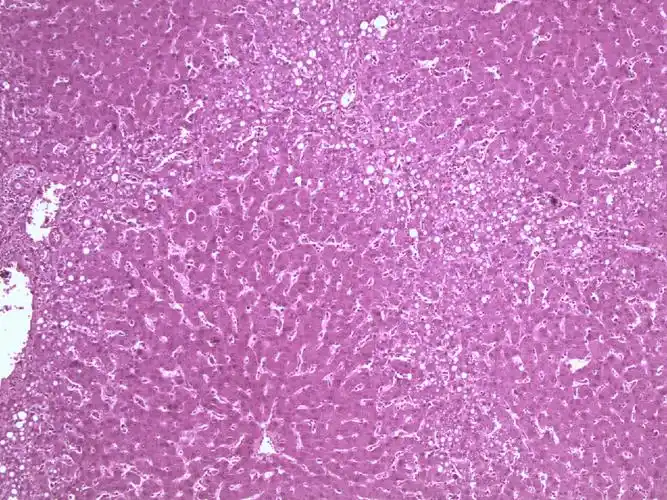

基于深度学习的结直肠癌全视野数字病理切片分子分型识别研究